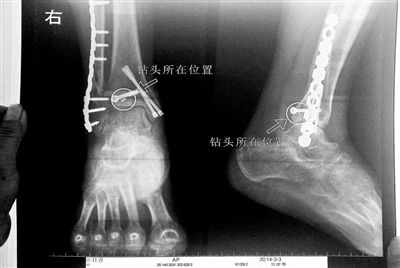

胡女士的腿部X光圖

看著X光片中自己腿內(nèi)的異物,胡女士就感到莫名的擔(dān)憂。胡女士于2013年3月在北京市豐臺(tái)區(qū)右安門醫(yī)院進(jìn)行了一次骨折手術(shù),術(shù)后醫(yī)生才發(fā)現(xiàn)手術(shù)時(shí)用來(lái)打眼用的鉆頭不慎遺留在了胡女士的骨頭中,并且無(wú)法取出。

近日,在豐臺(tái)區(qū)右安門醫(yī)院,北京青年報(bào)記者見到了胡女士,她走起路來(lái)顯得一瘸一拐,腿腳并不利索。在她帶來(lái)的X光片上,可以清晰地看到,有一個(gè)異物存在于腿內(nèi)部。

“我當(dāng)時(shí)就嚇蒙了,怎么會(huì)有一個(gè)鉆頭在骨頭里?”胡女士余悸未消地說(shuō),第二天拍攝的X光片顯示,2厘米左右的鉆頭遺留在她右腳腳踝上部的骨頭內(nèi)。

胡女士說(shuō),當(dāng)時(shí)旁邊的醫(yī)生勸慰自己,稱鉆頭留在腿里并不會(huì)有什么問(wèn)題。出院后,胡女士每個(gè)月都會(huì)來(lái)醫(yī)院做復(fù)查,拍X光片。她說(shuō),每次都能夠清晰地看見自己骨頭里的那個(gè)明晃晃的“小東西”。

“留在她腿里的鉆頭確實(shí)無(wú)法取出?!毙熘魅谓忉屨f(shuō),按常理說(shuō),鉆頭不應(yīng)該斷在里面,但現(xiàn)在事情確實(shí)發(fā)生了。鉆頭沒(méi)有折在關(guān)節(jié),而是在跖骨內(nèi),跖骨主要起支撐作用,不像關(guān)節(jié)那樣起活動(dòng)作用,而且這個(gè)部位比較質(zhì)密,并非像肌肉要經(jīng)?;顒?dòng)受到擠壓。